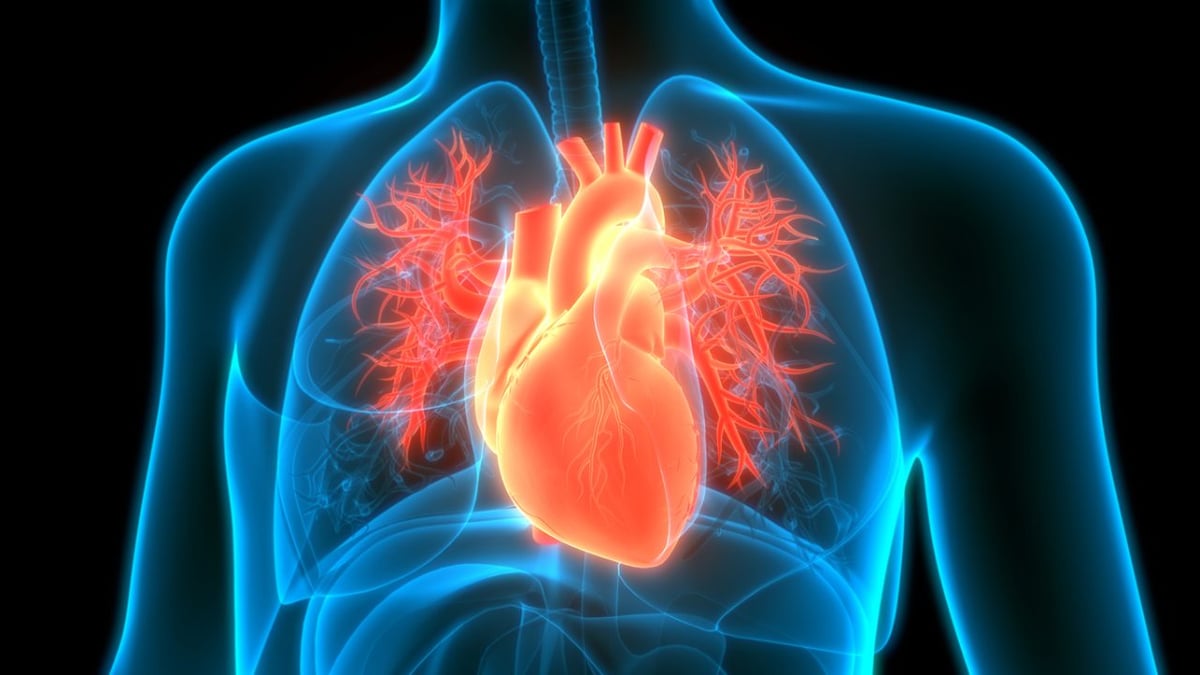

Das Herz (fachsprachlich Cor) ist ein lebenswichtiges Organ und zentraler Teil des Herz-Kreislauf-Systems. Es liegt im Brustkorb zwischen beiden Lungenflügeln und dient der Aufrechterhaltung des Blutkreislaufes. Im rechten Herzen kommt das sauerstoffarme Blut aus dem Körperkreislauf an und wird über die Lungenarterien durch die Lunge gepumpt. Das mit Sauerstoff angereicherte und von Kohlendioxid befreite Blut kommt im linken Herzen an. Es wird über die Hauptschlagader (Aorta) im ganzen Körper verteilt. Pro Minute passieren 5 bis 6 Liter Blut das Herz. Durch Anpassung der Herzfrequenz und des Schlagvolumens kann die Menge des minütlich gepumpten Blutes deutlich gesteigert werden. Dies dient der Anpassung an körperliche Belastung oder Stresssituationen. Den Organen und Muskeln wird auf diese Weise mehr Sauerstoff zur Verfügung gestellt. Der Herzmuskel selbst wird über die Herzkranzgefäße (Koronararterien) versorgt, die kurz hinter dem Herzen aus der Hauptschlagader abgehen.

Die Anatomie im Herz ist sehr komplex. Ein menschliches Herz ist im gesunden Zustand etwa faustgroß. Es liegt im Brustkorb zwischen beiden Lungen, gut geschützt von den Rippen und umliegenden Organen. Funktionell werden ein rechtes und ein linkes Herz unterschieden. Im rechten Herzen kommt das Blut über die obere und untere Hohlvene aus dem Körperkreislauf an. Der Sauerstoff aus dem Blut ist weitgehend verbraucht und es enthält viel Kohlendioxid. Gleichzeitig ist es reich an Nährstoffen, da das nährstoffreiche Blut aus dem Darm über die Leber ebenfalls dem rechten Herzen zugeführt wird. Über das rechte Herz gelangt das Blut in die Lungenarterie (Arteria pulmonalis). In der Lunge wird es mit Sauerstoff angereichert und von Kohlendioxid befreit. Über die Lungenvenen (Vena pulmonalis) fließt das Blut in das linke Herz. Es ist reich an Sauerstoff und Nährstoffen. Die linke Herzkammer pumpt das Blut anschließend in die Hauptschlagader (Aorta), von dort aus wird es im Körper verteilt.

Das Herz sitzt mittig im Brustkorb zwischen beiden Lungenflügeln, umgeben von den umliegenden Organen. Nach unten wird es vom Zwerchfell begrenzt.

Das Herz liegt mittig im Brustkorb. Aufgrund der größeren linken Herzkammer und der geneigten Herzachse liegt der überwiegende Teil des Herzens auf der linken Seite des Brustkorbs.